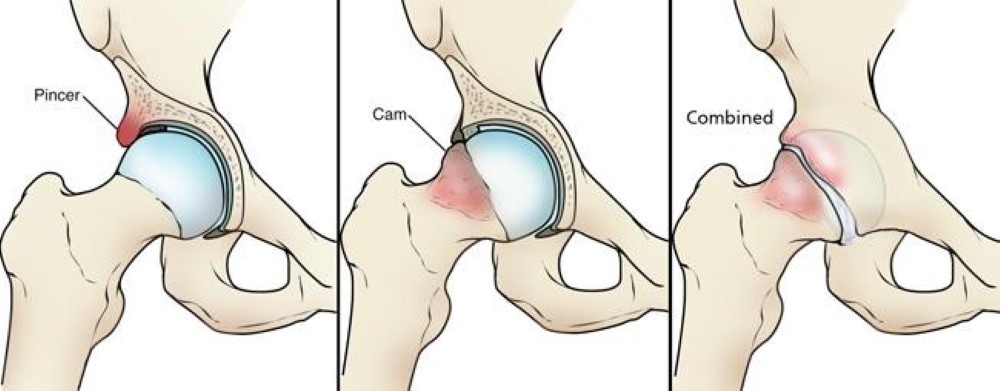

There are three types of anatomical variation which can lead to femoroacetabular hip impingement:

- Pincer: This type of impingement is caused by extra bone growth which extends over the rim of the acetabulum in the hip socket. The labrum can become pinched by the prominent rim.

- Cam: In this type of impingement, the ball has a more oval than round appearance. This means that the head cannot rotate smoothly in the acetabulum, creating friction when the ball hits the edge of the socket. This repeated friction can cause bony growth on the head of the joint, adding to further impingement.

- Combined: This means that both the cam and pincer types of FAI are present.

When these changes to the bone shape occur, they can cause the hip joint to pinch during movement, particularly affecting the labrum (the ring of cartilage around the socket). Repeated pinching can irritate or damage the labrum over time. This may lead to pain, especially during and after exercise, or when sitting for long periods.